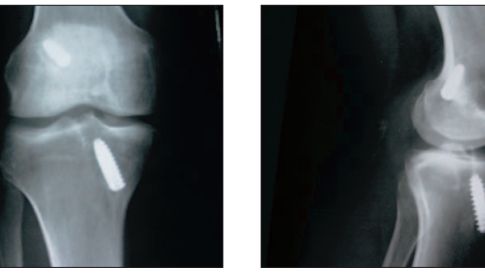

/ 8Zdjęcie RTG

Rtg pacjenta po rewizynej rekonstrukcji ACL z zastosowaniem allograftu